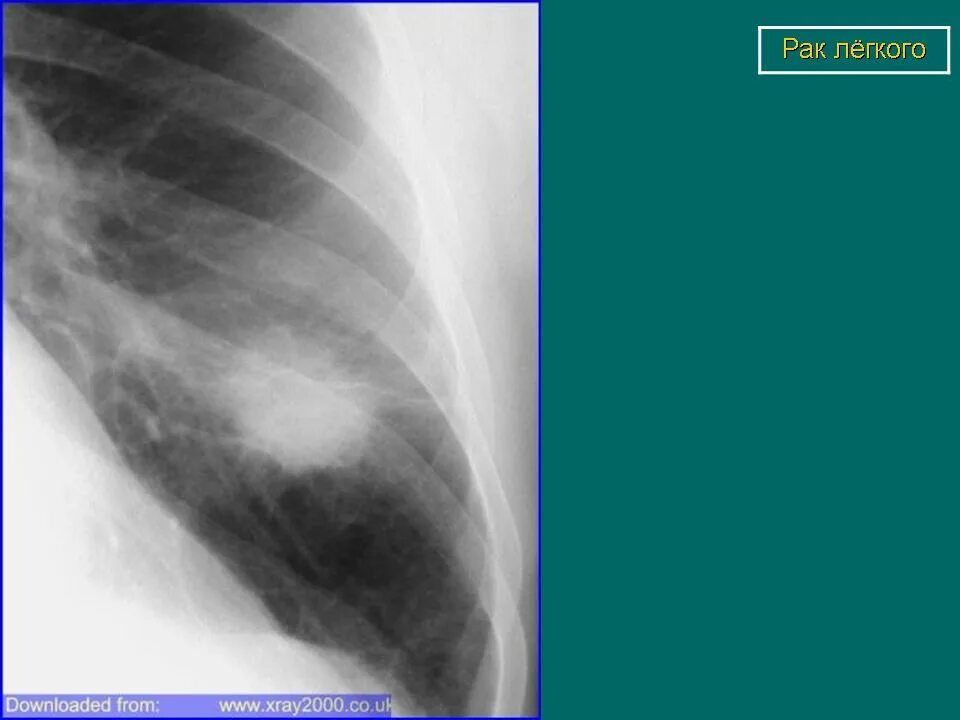

Лучевая при раке легких